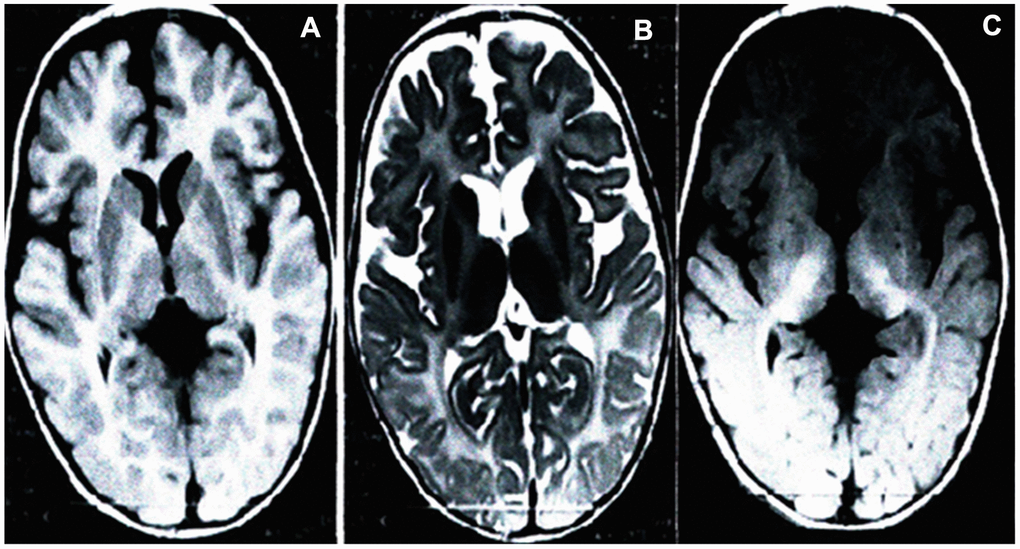

Brain MRI scans of the proband (the son of the pregnant woman) displays aberrant white matter and no normal myelin signal in the supratentorial structures, with homogeneously high signal intensities in the white matter on T1-weighted (Figure 1A), subcortical new fiber on the T2-weighted (Figure 1B) and fluid attenuated inversion recovery (FLAIR) images (Figure 1C). The cerebellar white matter lacking the normal dark myelin signal on T2-weighted images (Figure 1B), showing abnormal myelination of white matter in the brain. The brain MRI findings of the proband were consistent with PMD.

Figure 1. Brain MRI of the proband. Scans showed significantly development delay of white matter, poor myelin formation, close to the level of myelin development in neonates, and reduced volume of white matter throughout the brain. Axial T1-weighted (A), T2-weighted (B) and FLAIR (C).